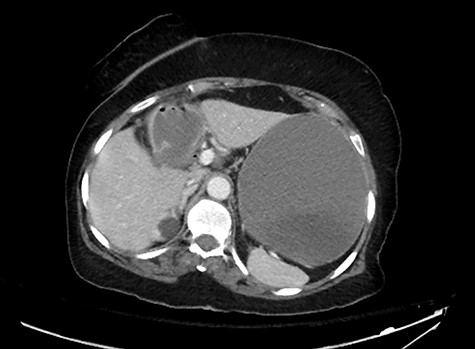

An 81-year-old woman with long history of gallstones was presented to the emergency department with persistent vomiting associated with progressive abdominal distension and inability to pass bowel motion or gases for the past 3 days. Examination showed stable vitals and distended abdomen. A computerized tomography (CT) scan showed high-grade small bowel obstruction in mid-ileum caused by a large impacted gallstone (Fig. 1). There was also a wide neck cholecystoduodenal fistula (Fig. 2).

A CT abdomen and pelvis scan showing a large stone in the small bowel.